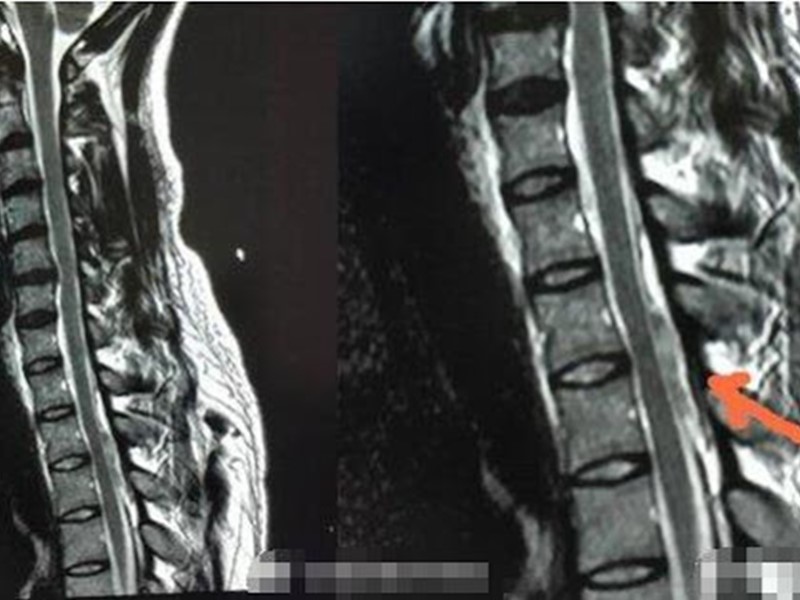

29岁小陈是前两星期六(10日)在家中做晨操时出事,他被送到医院,在做检查阶段时又突然出现左下肢无力、麻木,无法正常行走,院方以其健康安全,最终收治入院。到晚上10时半,他双下肢已经不能活动了,肚脐以下没了知觉,出现截瘫状况。

翌日凌晨2时多,紧急被进入手术室,足足做了到3个多小时手术,医生为他取出血凝块,目前他恢复良好。

医生指,小陈患自发的脊髓硬膜外血肿(SSEH)是一种相对罕见,但却能致残的疾病,病发病率为百万分之一。估计他的椎管一直存有隐患,做掌上压时增加腹压,引致血管破裂。